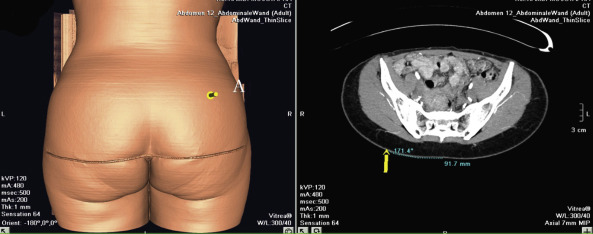

In the case of a perforator flap, a fusiform skin island is drawn over the perforators, ideally centered on selected perforators. The main perforators are localized by a handheld 5–8 MHz Doppler probe in an area above or under the piriform muscle, for SGAP or IGAP flaps, respectively ( Fig. 44.3C ). Currently, we are using a new method for perforator mapping with a 64-slice spiral computed tomography (CT) scan ( Figs 44.4 , 44.5 ). This provides more accurate information concerning the vascular network and perforators. Choice of the perforator depends not only on the strength of the Doppler signal or the findings of the CT scan but also on the location of the perforator. Choosing the most remotely located perforator from the SGA exit will provide a longer pedicle, which is more suitable for microanastomosis ( Figs 44.4 , 44.5 ).

In the case of perforator flaps, the preoperative markings are adjusted, depending on the location of the perforators. The patient is positioned lying on the operative table ( Fig. 44.3C ). A line is drawn between the PSIS and the coccyx (PSIS-C). The position of the piriform muscle is located by connecting the middle of the PSIS-C line with the superior edge of the greater trochanter (T) of the femur. The relatively constant anatomy of the superior gluteal artery and the presence of a low number of perforators that cross the fascia perpendicularly make it rather easy to preoperatively identify the location of the perforators by unidirectional Doppler flowmetry or spiral CT scanner.